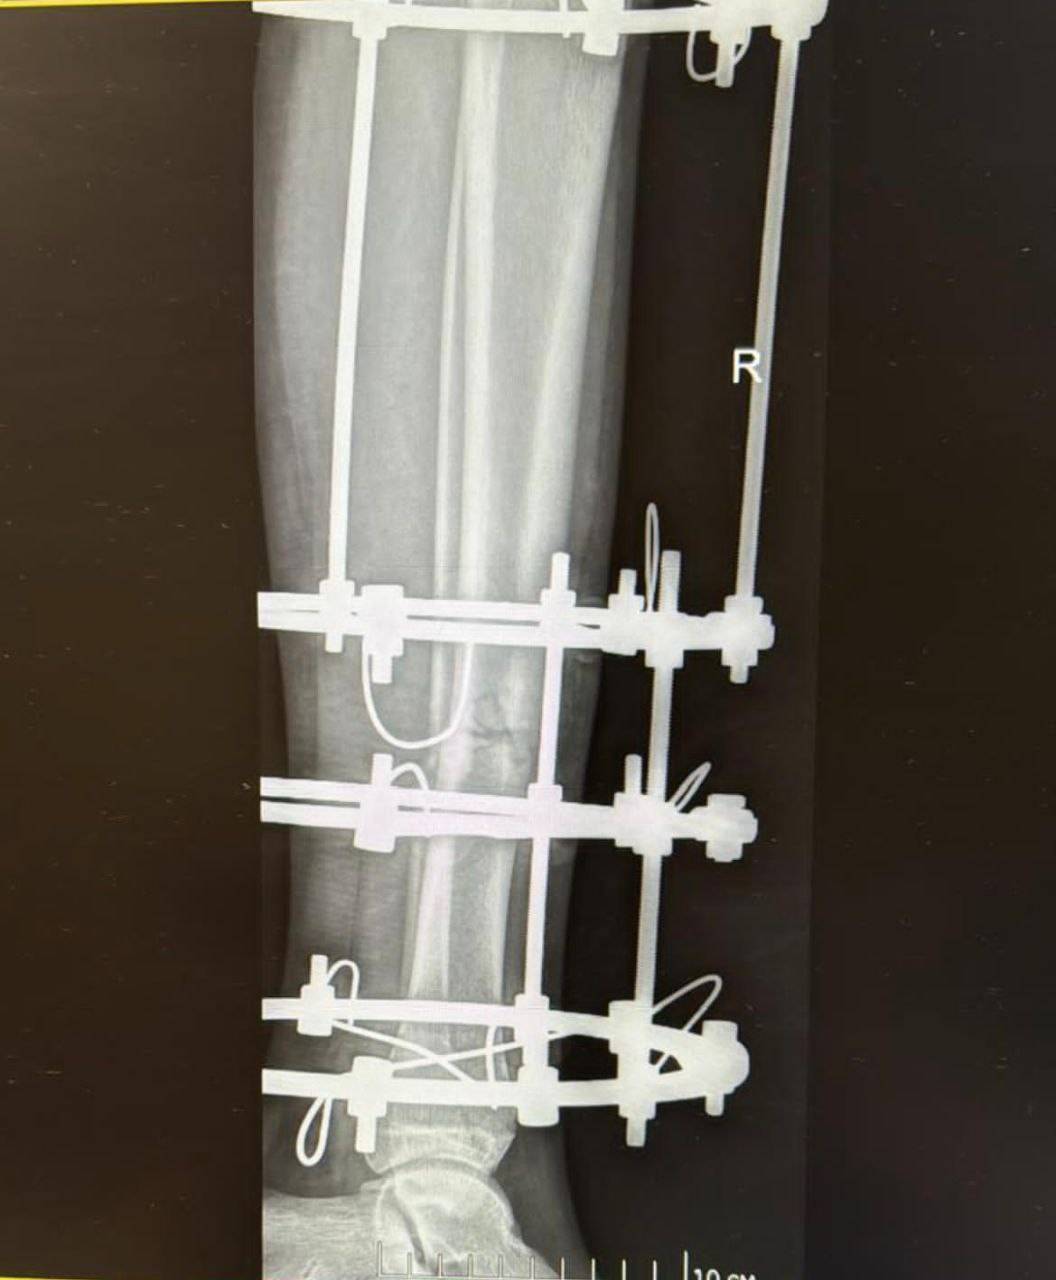

Его друг получил лишь лёгкие ушибы коленей. Его товарищ отделался незначительными повреждениями колен. Прибывшие медики немедленно доставили пострадавшего в городскую клиническую больницу Владивостока. Диагноз врачей оказался суровым: открытый перелом обеих берцовых костей левой конечности.